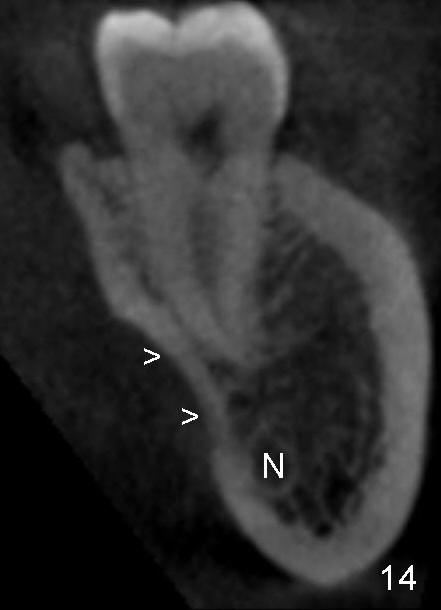

The submandibular (gland) fossa, or lingual (L) concavity (Fig.1 <), is more pronounced in the lower 2nd molar (7) that that of the first (6) (Fig.1 vs.2, 4 vs.3, the same patient). The lingual concavity may be mild (Type I, <2 mm depth, Fig.9-11), moderate (Type II, 2-3 mm, Fig.1,4, 12) and severe (Type III, >3 mm, Fig.13,14 (same patient)).

In addition, it is important to control the depth of the osteotomy. For freshly healed socket and immediately post-extraction socket, it should be safe to place a 11 mm long bone-level (Fig.15,16) or 14 mm gingival level (Fig.13,18) implant or less. For the same length, it appears safer to use a tapered implant (Fig.9,13,18) than cylindrical one (Fig.15,16).